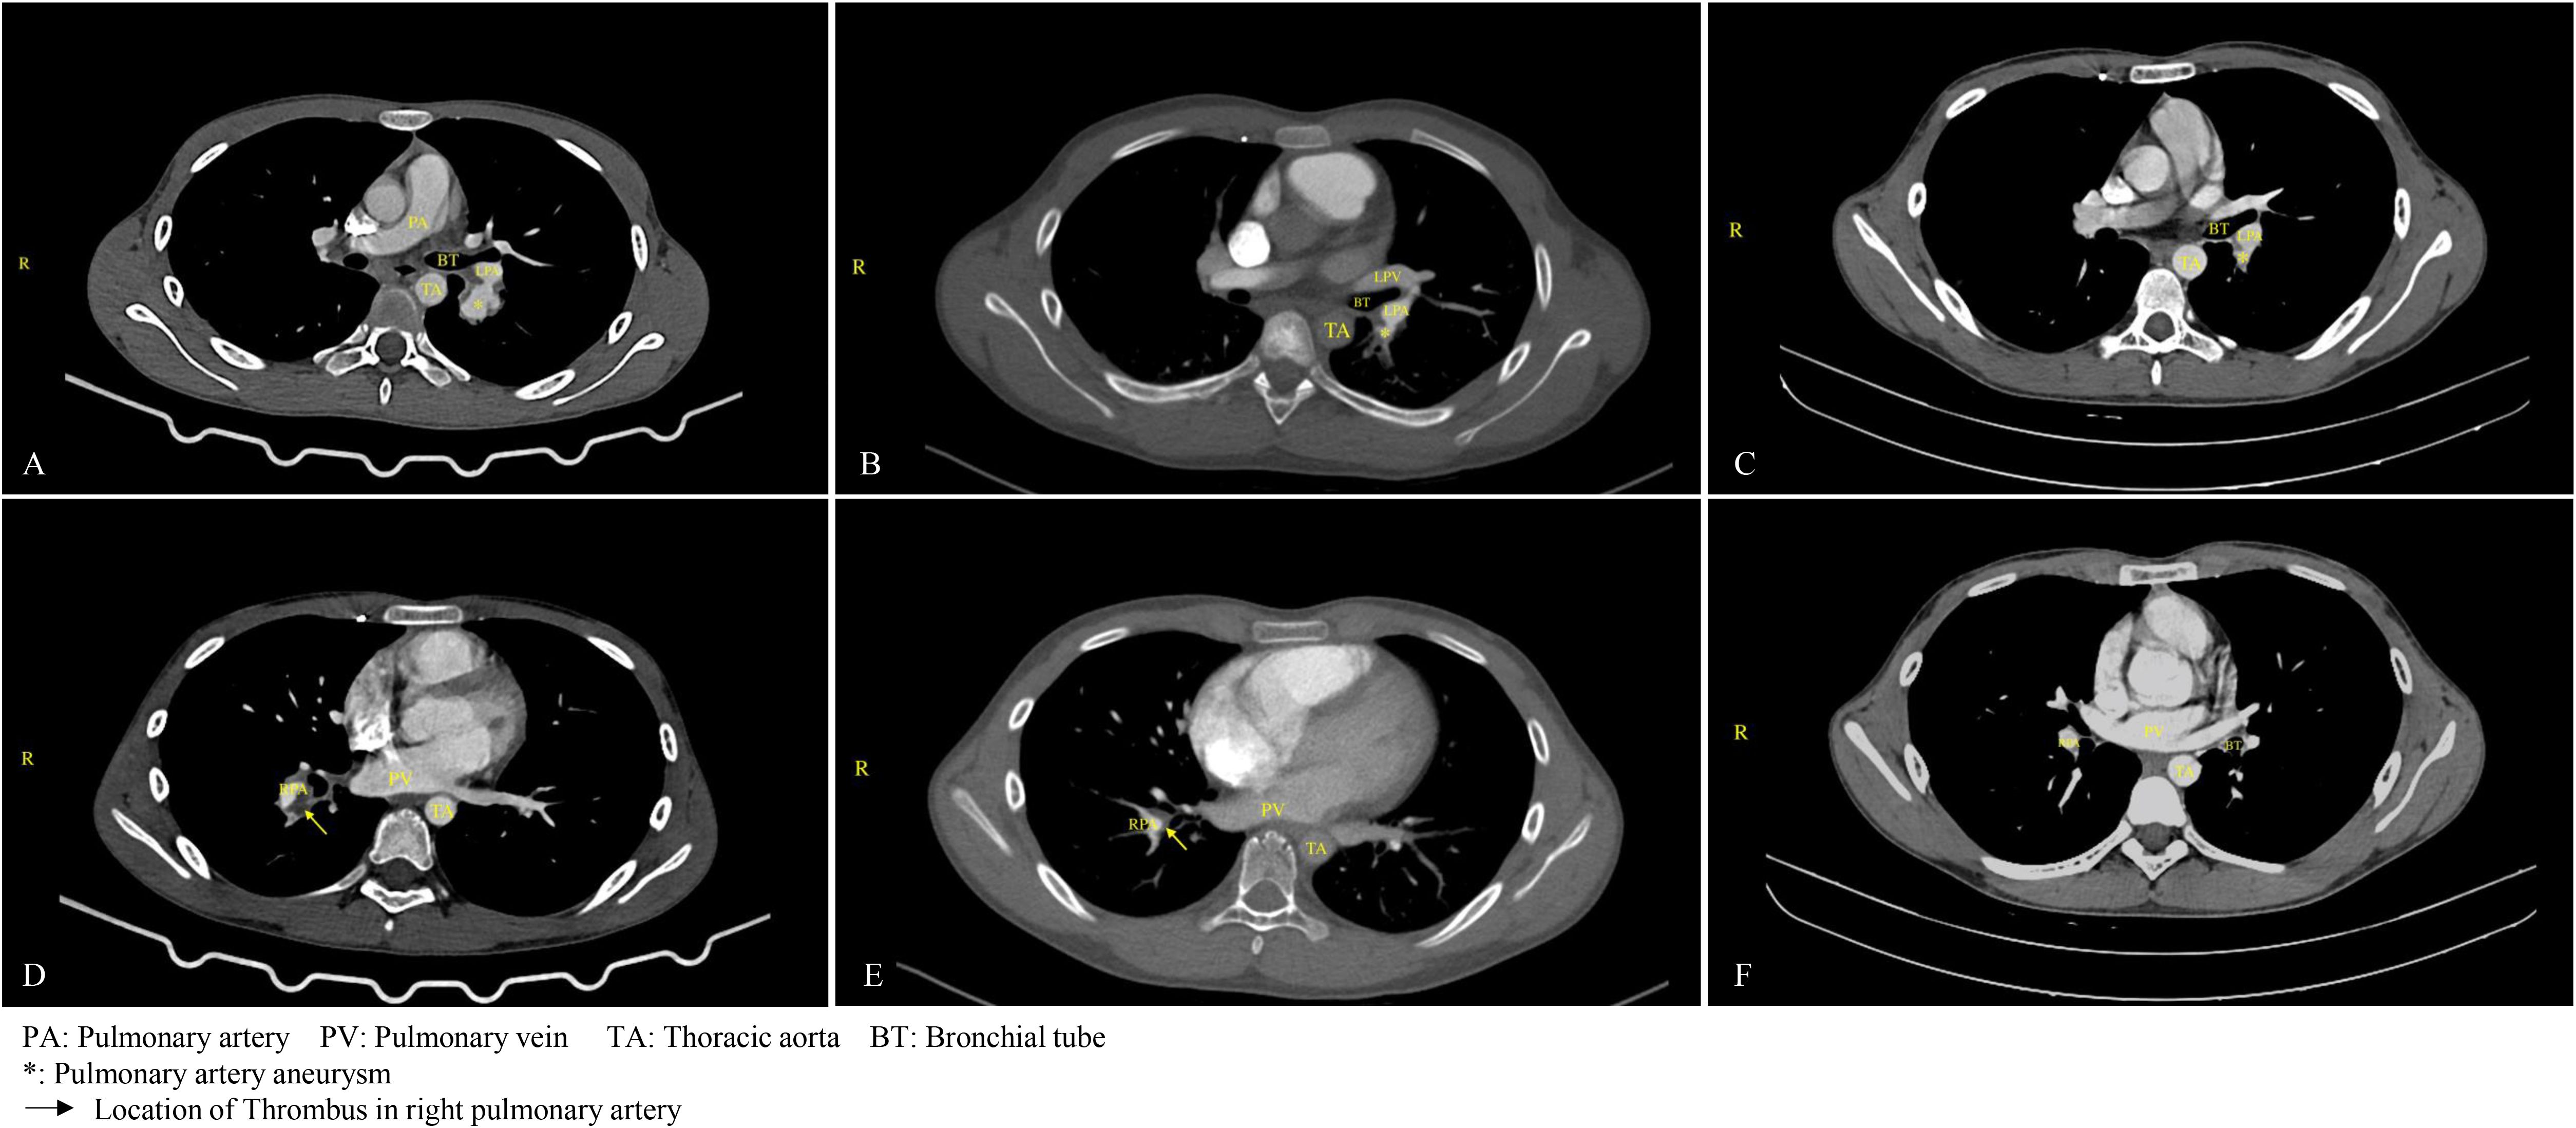

Hemoptysis was treated with bronchial embolization. Medical treatment was initiated with subcutaneous enoxaparin, high-dose oral prednisone (40mg qd), and diosmin to improve the leg heaviness. During treatment, color Doppler ultrasound showed reduced thrombosis in the left external iliac and common femoral veins with partial recanalization. Warfarin monotherapy continued after the INR reached the target range. At discharge, the rash and oral ulcers had resolved. After that, low-dose prednisone and long-term warfarin anticoagulation were administered. Two months following discharge, the patient consulted with a rheumatologist, who strongly recommended the administration of adalimumab, an anti-tumor necrosis factor (TNF) agent. However, this recommendation, along with the suggestion to use cyclophosphamide, was declined by the patient’s guardian. After extensive discussions with the patient’s family, azathioprine was selected as an alternative for immunotherapy and has been administered continuously to date. A comprehensive overview of the medical regimen is detailed in Table 1. Throughout the six-month follow-up period, the child’s daily academic and extracurricular activities remained unaffected. A computed tomography angiography (CTA) of the lungs conducted four months post-discharge revealed the resolution of the thrombus in the main pulmonary artery, with only minor embolisms persisting in a few small branches. A subsequent CT scan performed one year later indicated the complete resolution of the pulmonary embolism, with no significant alterations observed in the venous thrombosis of the left lower extremity (Figure 1).

Figure 1. Changes in pulmonary aneurysm and thrombus before and after treatment. (A) On March 18, 2024, the patient was diagnosed with a pulmonary aneurysm. (B) A follow-up examination on August 1, 2024, indicated no significant change in the patient's pulmonary aneurysm compared to the previous assessment. (C) By August 4, 2025, a follow-up examination of the child revealed a significant reduction in the aneurysm. (D) On March 18, 2024, thrombosis was identified in the upper posterior segment of the left lower lobe, along with aneurysmal dilation of the pulmonary artery in the right lower lobe accompanied by thrombus formation, and thrombus formation in the branches of the pulmonary arteries in both lower lobes. (E) After four months of anticoagulation treatment, as of August 1, 2024, the thrombus in the main pulmonary artery had resolved, although embolization persisted in a small branch of the pulmonary artery in both lower lobes. (F) By August 4, 2025, a follow-up examination of the child confirmed the resolution of the pulmonary thrombus.